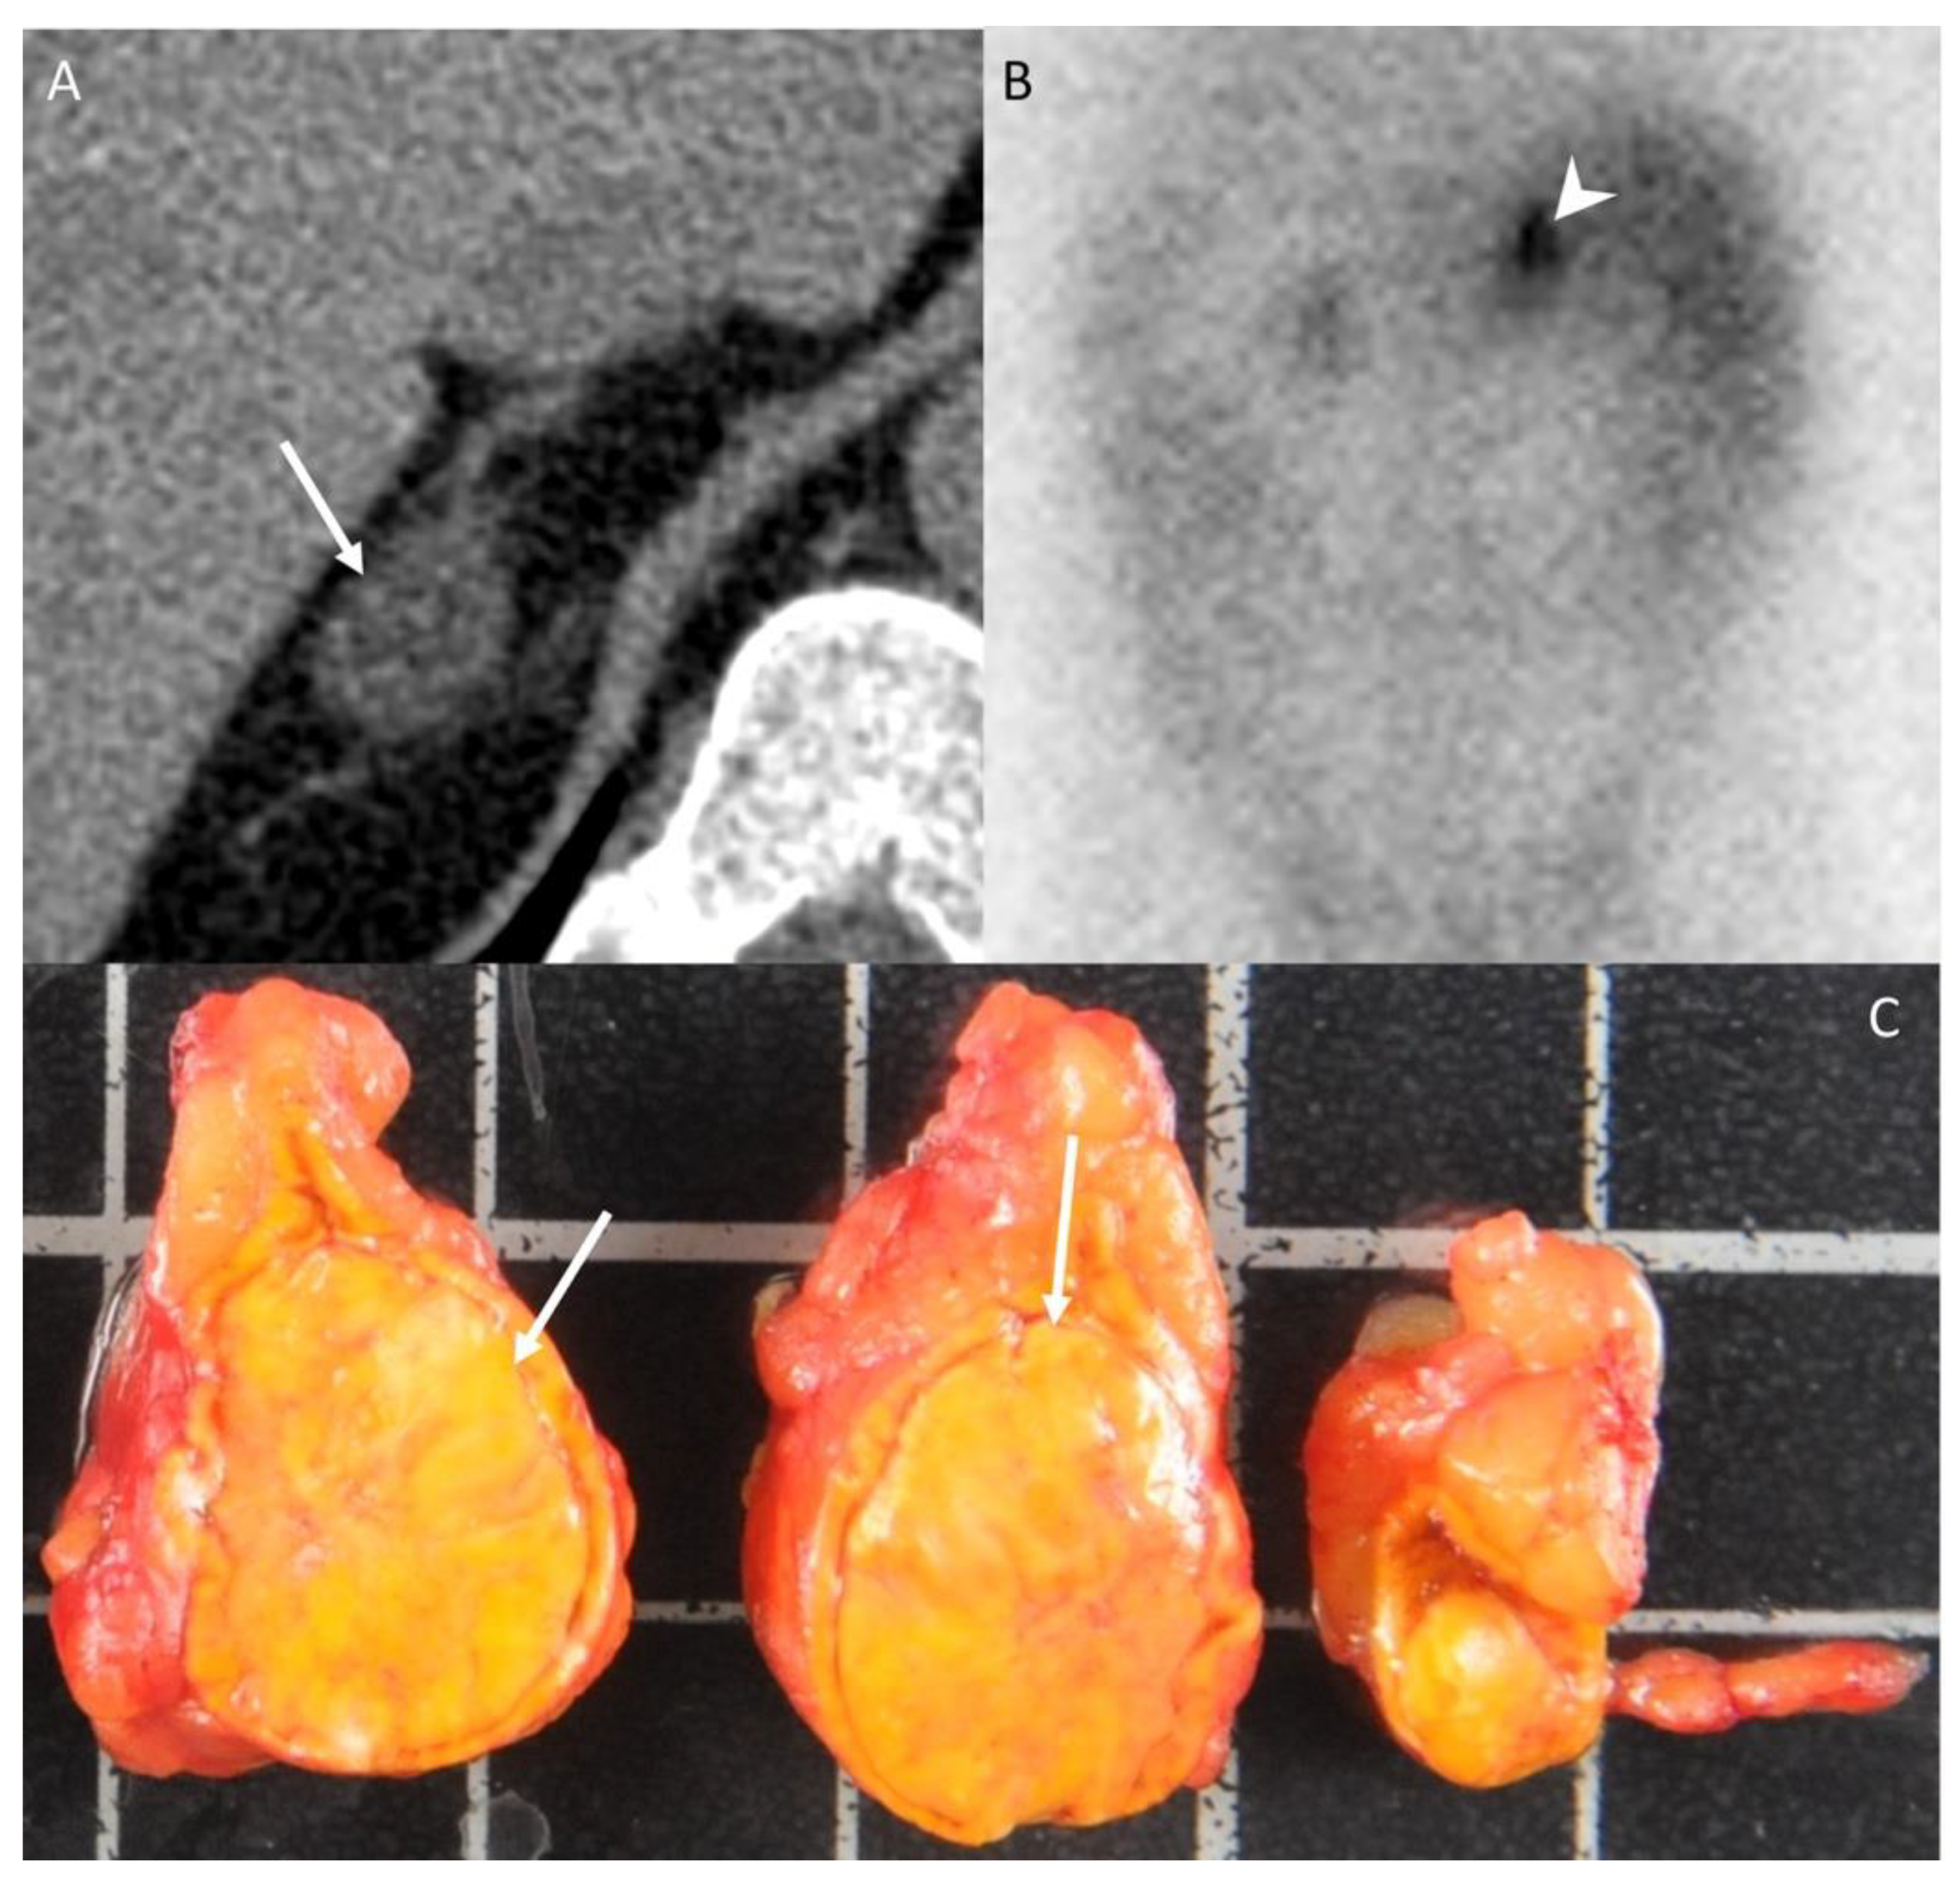

- Kostiainen, I.; Hakaste, L.; Kejo, P.; Parviainen, H.; Laine, T.; Loyttyniemi, E.; Pennanen, M.; Arola, J.; Haglund, C.; Heiskanen, I.; et al. Adrenocortical carcinoma: Presentation and outcome of a contemporary patient series. Endocrine 2019, 65, 166–174. [Google Scholar] [CrossRef] [PubMed]

- Park, S.Y.; Park, B.K.; Park, J.J.; Kim, C.K. CT sensitivities for large (>/=3 cm) adrenal adenoma and cortical carcinoma. Abdom Imaging 2015, 40, 310–317. [Google Scholar] [CrossRef] [PubMed]

- Kedra, A.; Dohan, A.; Gaujoux, S.; Sibony, M.; Jouinot, A.; Assie, G.; Groussin Rouiller, L.; Libe, R.; Bertherat, J.; Soyer, P.; et al. Preoperative Detection of Liver Involvement by Right-Sided Adrenocortical Carcinoma Using CT and MRI. Cancers (Basel) 2021, 13, 1603. [Google Scholar] [CrossRef] [PubMed]